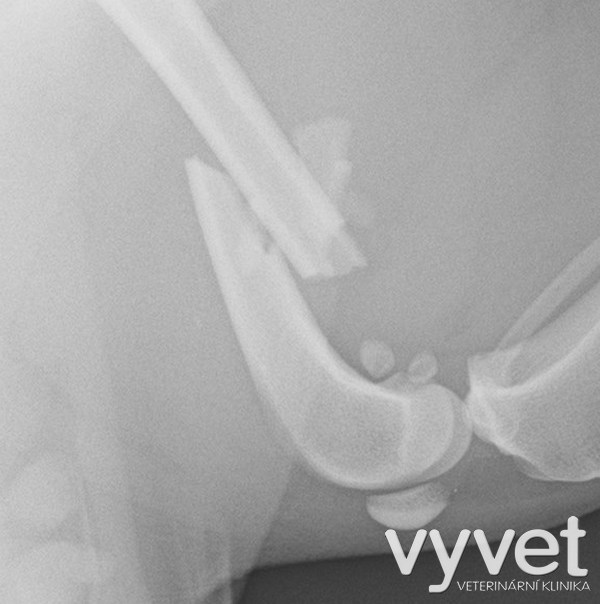

Nejčastějším problémem dlouhých kostí jsou zlomeniny (fraktury)

Rozdělujeme je do několika skupin podle charakteru, množství fragmentů, průběhu linie lomu, dislokace, stability atd.

Je mnoho popsaných metod fixací fraktur. Neinvazivní metodou je přikládání fixačních obvazů a kastů. Tento typ fixace však není ideální, protože nejsme schopni u zvířat zabezpečit dostatečně dlouhou dobu klidu pro srůst kosti. Ideální metodou je invazivnější přístup a to chirurgická repozice s následnou fixací osteosyntetickým materiálem.

Na našem pracovišti používáme zejména ploténky a hřeby.